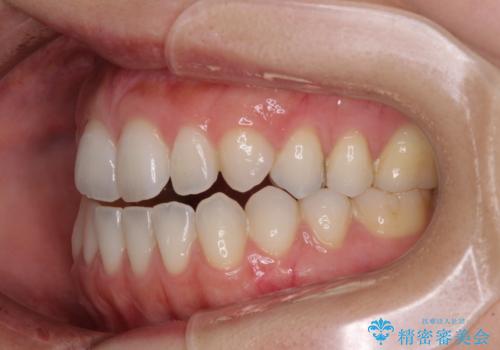

【モニター】狭い上顎歯列とオープンバイト 急速拡大装置を用いた矯正治療

- インビザライン

- 2年1ヶ月

上顎歯列が狭窄していたため、急速拡大装置により上顎骨を側方に拡大し、その後インビザラインにて矯正治療を行うこととしました。

舌の突出癖が開咬の原因であったので、改善のための舌トレーニングを行っていただきました。

舌トレーニングは後戻りにも大きく影響するため、とても重要なトレーニングです。